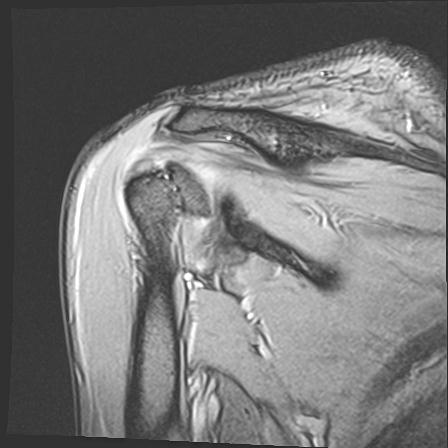

60058 3/9 11/4 右肩 2R+MRI 73歳男性 肩腱板損傷